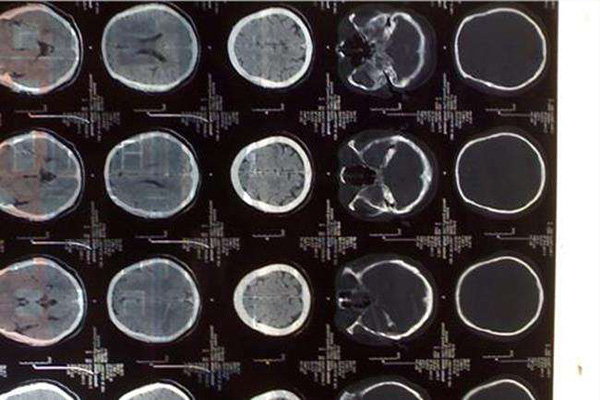

脑水肿,脑积水的分类及图像表达,一文归纳

各类型脑水肿的鉴别